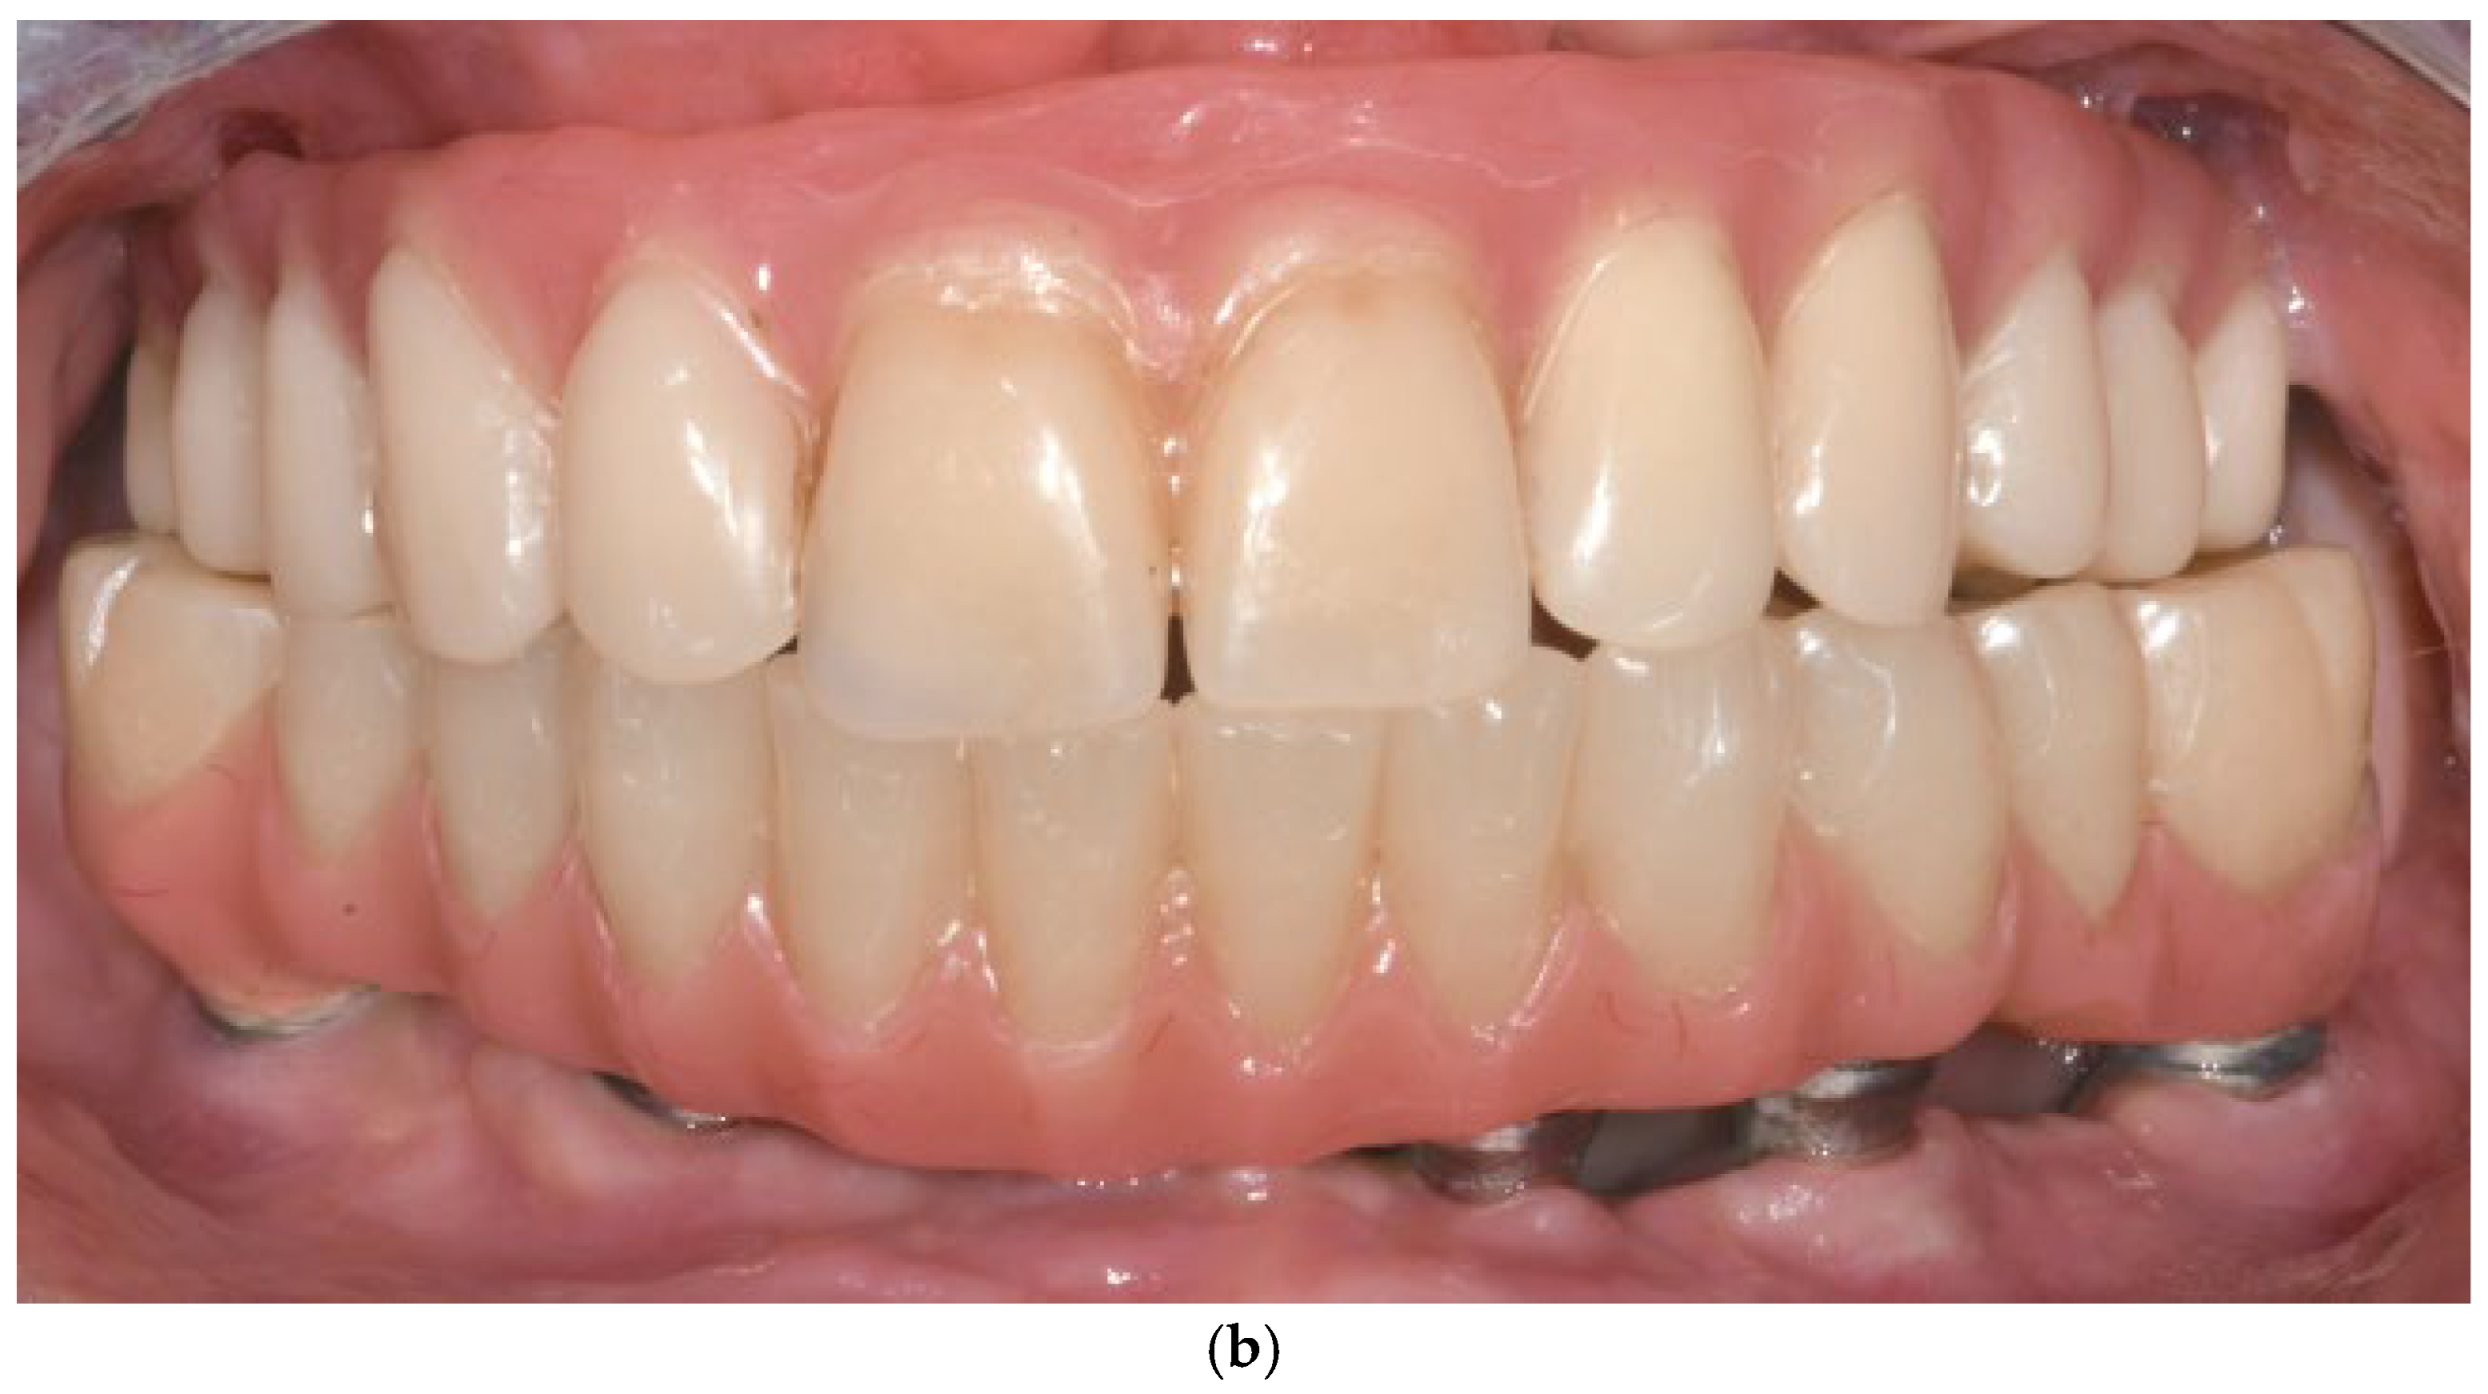

Patients were followed up at 3 and 6 months postoperatively, and then annually. Follow-up assessments included clinical evaluation and panoramic imaging; CBCT scans were obtained when necessary to monitor implant fit, peri-implant tissue response, and bone contour stability. All implants remained functionally stable throughout the observation period. The follow-up period ranged from 12 to 60 months, with a mean duration of 36.2 months (Figure 6a,b). Each patient underwent routine hygiene sessions every six months and an annual special session with prosthesis removal for thorough cleaning.

Figure 6.

(a) A panoramic radiograph of the patient at 5-year follow-up. (b) Intraoral clinical image of the patient at 5-year follow-up.